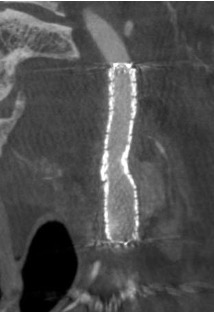

頸動脈狭窄症に対する頸動脈ステント留置術(CAS)

頸動脈狭窄症とは首の動脈が細くなる病気で,脳梗塞の原因となります。狭窄部にステントを留置することでプラークの破綻を防ぎ,脳梗塞を未然に防ぎます。ステント留置後に希釈造影剤を用いた回転撮影からMPR像を構築し,血管内腔評価を行います。

MPR像